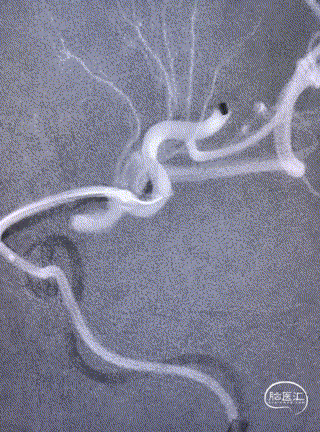

小血管血栓取栓病例

一例左侧大脑中动脉M3段闭塞远端

抽吸导管血管再通治疗

作者:高军、温昌明